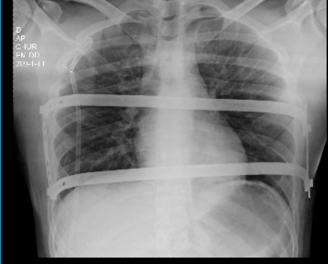

Veja casos de antes e depois